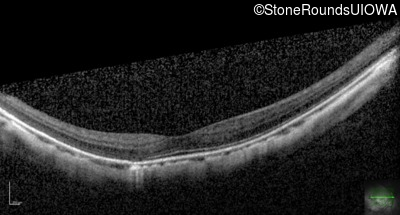

XL Congenital Stationary Night Blindness (IA2fi)

XL Congenital Stationary Night Blindness

NYX

Trp273Stop TGG>TGA

XL

Gene:

Allele 1:

Inheritance: